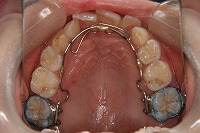

反対咬合を主訴に来院された、右側唇顎裂の10歳6ヵ月の女の子です。診断「右側唇顎口蓋裂で反対咬合を伴う」1期治療で反対咬合の解消と上顎の前歯の並びを修正しました。2期治療は抜歯をせず治療を行いました。